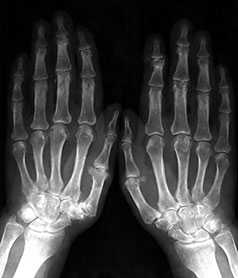

Стандартная рентгенография кистей проводится в прямой проекции. Пальцы расположены вместе, кисти лежат ровно на кассете на одной линии с осью, проходящей через предплечья и запястья.

Начальные проявления (соответствуют 1-2 стадиям артроза по Kellgren):

Небольшие заострения краев или остеофиты с нерезким субхондральным остеосклерозом; мелкие, субхондрально расположенные кисты при нормальной или слегка суженной суставной щели, мелкие кальцификаты в мягких тканях в области боковых краев суставных поверхностей костей.

Выраженные изменения (соответствуют 3-4 стадиям артроза по Kellgren):

Умеренно выраженные или крупные остеофиты, деформация краев суставных поверхностей, значительное сужение суставных щелей, остеосклероз (узелки Гебердена в дистальных межфаланговых суставах и узелки Бушара в проксимальных), кисты со склеротическим ободком, краевые дефекты суставных поверхностей, при этом костные выступы с одной стороны могут вклиниваться в другую. Обычно краевые дефекты окружены зоной остеосклероза (рис. 3).

Рис. 3. Обзорная Rо-графия кистей.

Множественные артрозы дистальных и проксимальных межфаланговых суставов. Множественные узелки Гебердена и Бушара. Выраженный артроз 1-го левого запястнопястного сустава